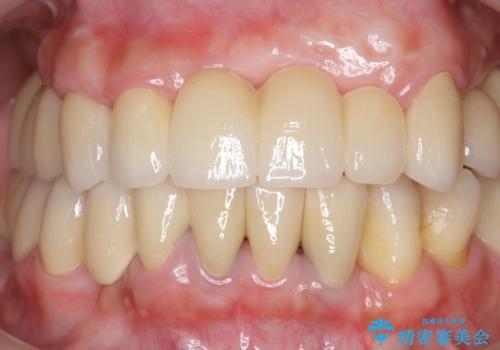

歯周病 全顎治療

- 前歯の見た目、入れ歯による噛めないことの改善を求めて来院されました。

検査により全顎的な歯周病治療、欠損のインプラント補綴、根管治療が必要な状態であることをお伝えし、治療を計画します。

失ってしまった機能を回復し、今後歯を失わないよう残せる歯に歯周病治療を行い、安定した咬合を確立することで長期的に問題なく噛めるような口腔内環境を達成できるようになると考えます。